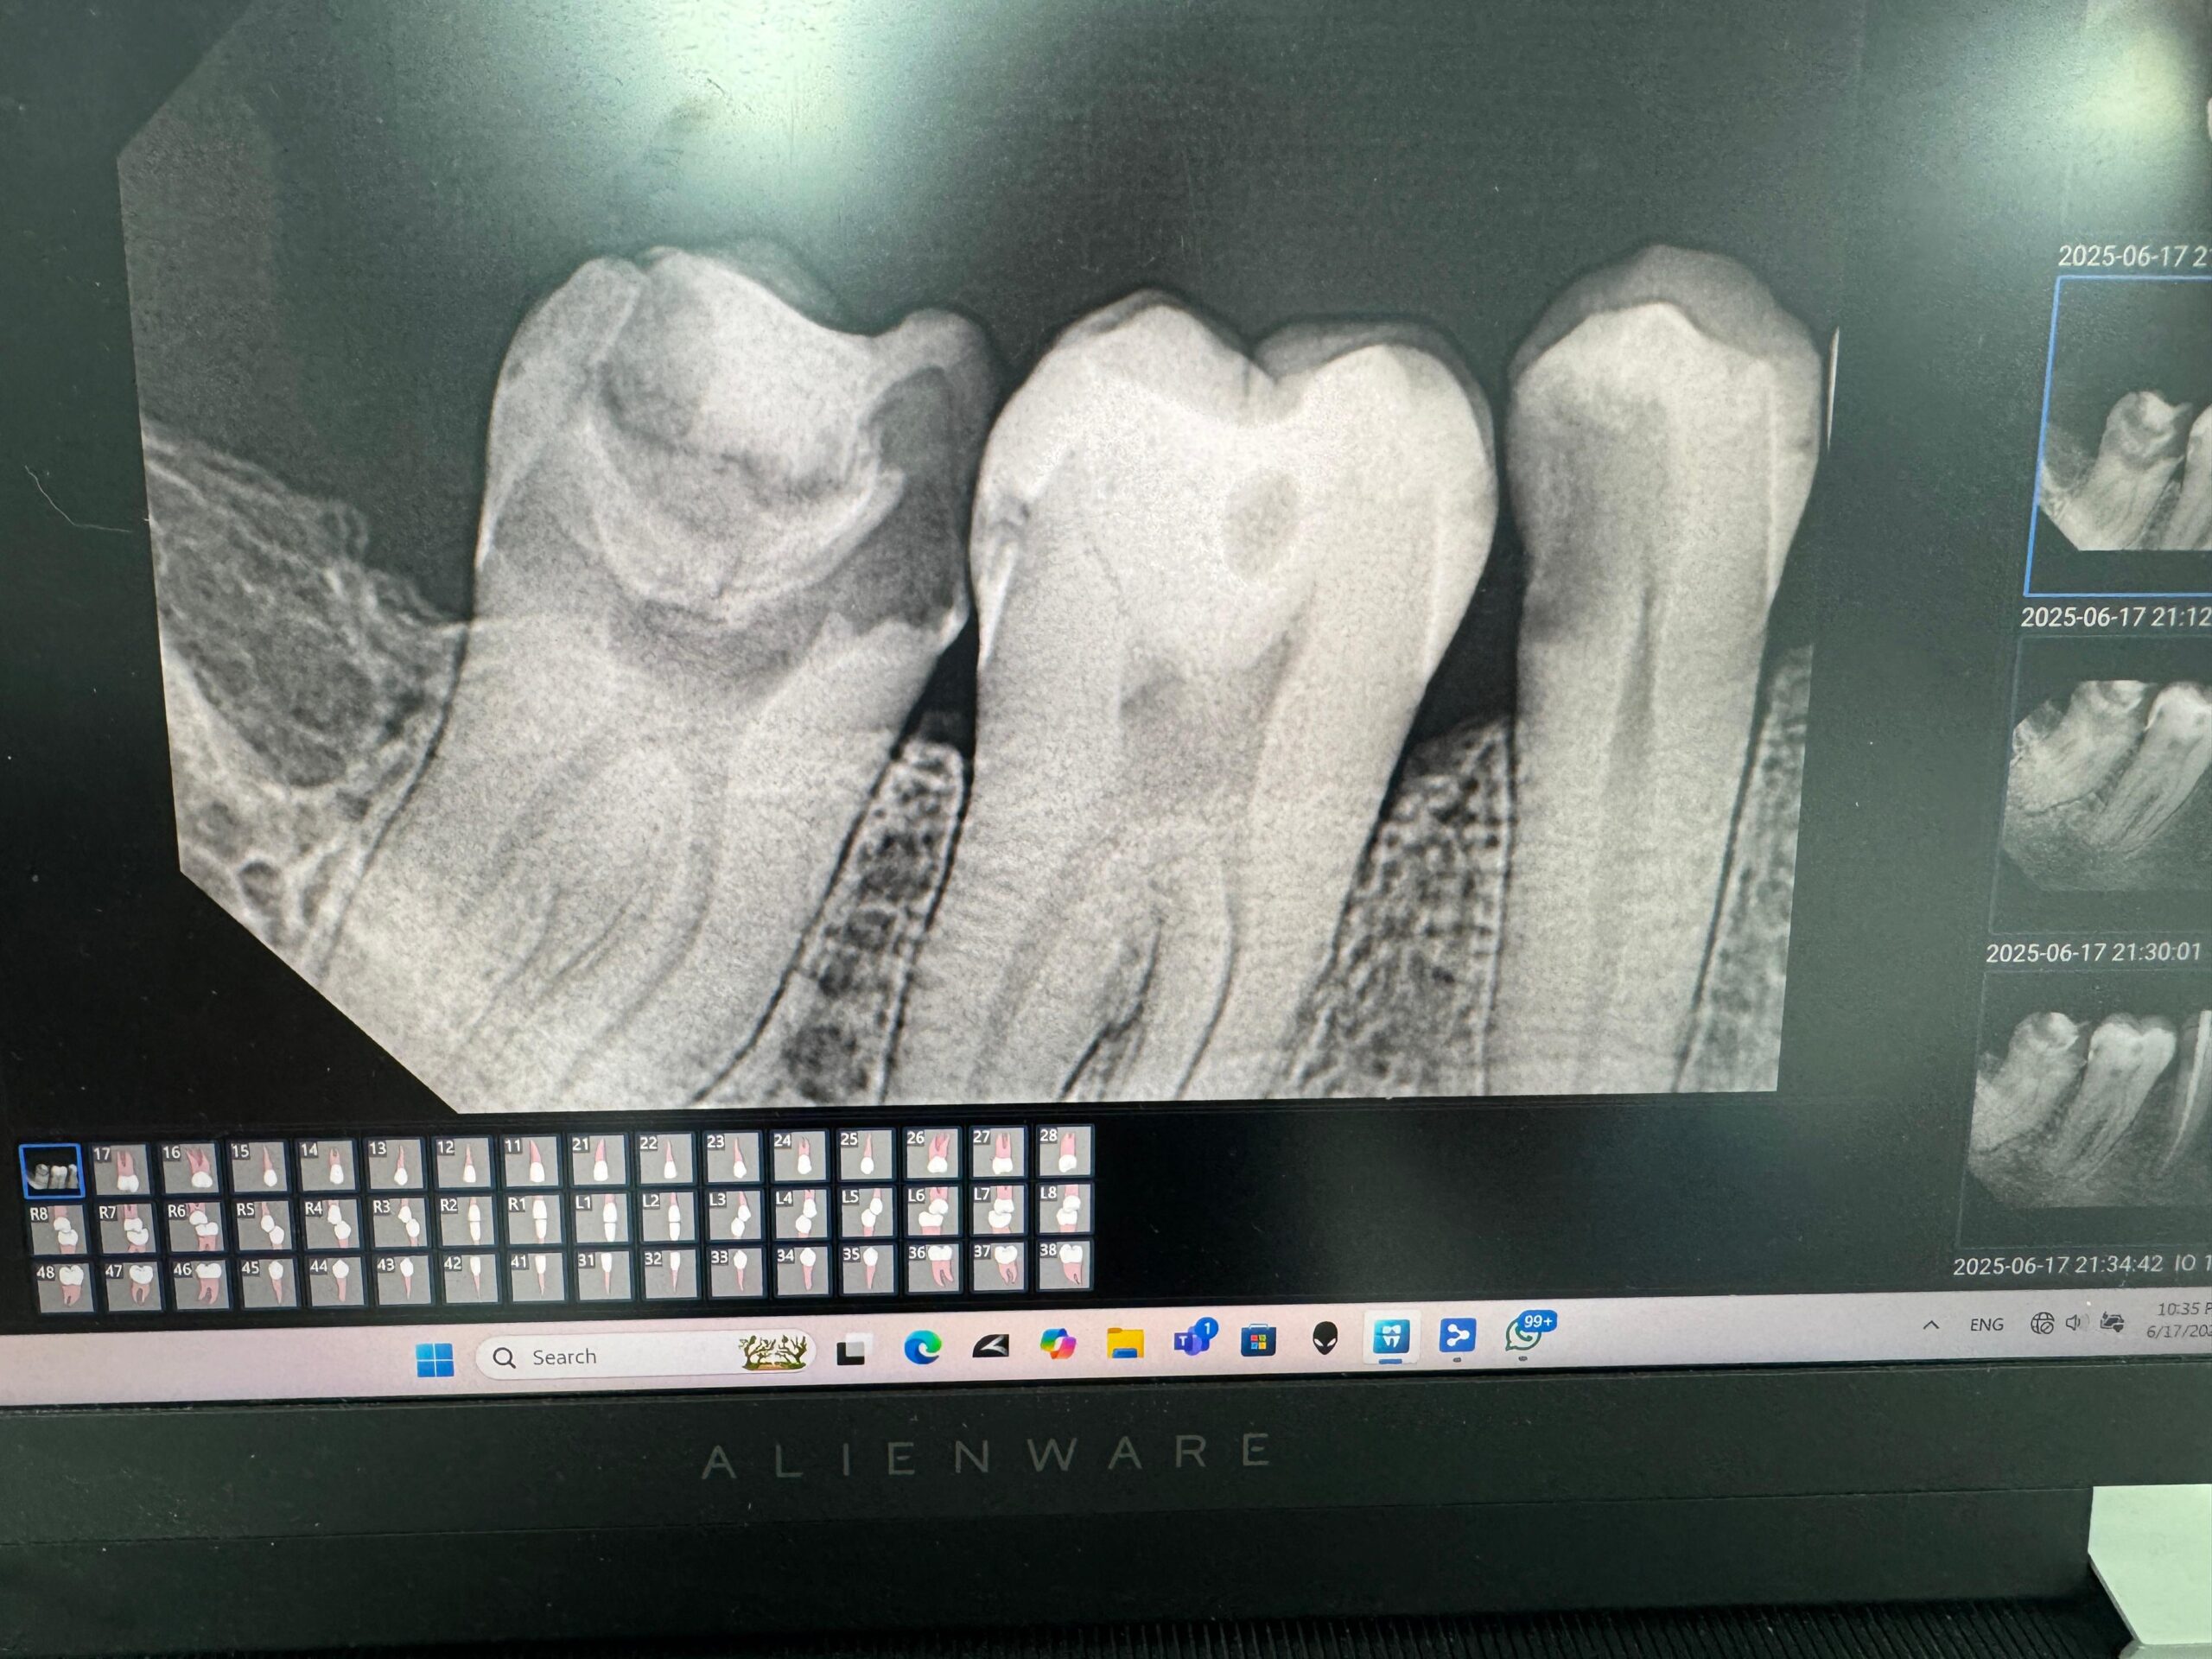

• Accurate diagnosis of nerve condition using the latest radiology equipment.

• Using modern root canal filling devices to ensure accurate and efficient cleaning of the nerve canals.

• High-quality filling materials prevent bacteria from seeping in and preserve the tooth for many years.